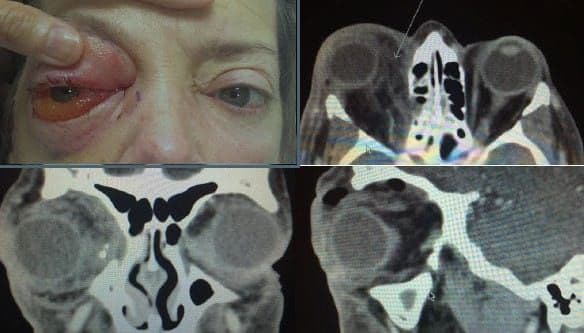

Зображення: орбітальний перелом

Зобр. 15. Комп’ютерна томограма, що демонструє переломи дна та медіальної стінки лівої орбіти.

Автор фотографії: Maj Brett Davies.